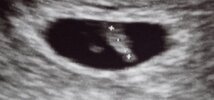

Wiem że łatwo sie mówi ale bądź spokojna, stres nie pomoże. Dobrze ze masz wizyte tak szybko już na jutro. Moze poprostu zle zaznaczył, Będzie dobrze, musi być dobrzeJa jestem po kolejnym USG - zarodek wg niego ma dopiero 6mm (w zeszły poniedziałek miał 3mm). Widzę, że lekarz niedokładnie zmierzył CRL nie obejmując całego maluszka, ale i tak umieram ze stresu. Zapisałam się od razu na jutro do innego lekarza i mam nadzieję, że wszystko będzie ok![]()

Jeśli nie jesteś pewna tego lekarza a masz możliwość iść do innego to tak zrób, będziesz spokojniejsza po co masz się zamartwiać.Ja jestem po kolejnym USG - zarodek wg niego ma dopiero 6mm (w zeszły poniedziałek miał 3mm). Widzę, że lekarz niedokładnie zmierzył CRL nie obejmując całego maluszka, ale i tak umieram ze stresu. Zapisałam się od razu na jutro do innego lekarza i mam nadzieję, że wszystko będzie ok![]()